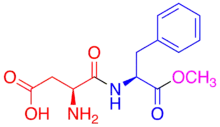

Aspartame

This sugar substitute, known on the market as NutraSweet (for baking purposes) or Equal, was discovered in 1965, but not approved by the FDA until 1981. It is 180 times as sweet as sucrose and contains 4 calories per gram, which is considered negligible. It is unstable in heat and decomposes in liquid during prolonged storage. However, although the aspartame may decompose in liquid, it is not hazardous for consumption. The break-down of aspartame only affects the quality of the beverage. Aspartame is a dipeptide consisting of two amino acids in an ester bond with methanol. Aspartic acid is at the N-terminus and phenylalanine is at the C-terminus where it bonds with methanol. Aspartame is metabolized in the gastrointestinal tract, where the peptide and ester bonds are broken, separating the amino acids and the methanol. The effects of the increase in methanol concentration from the breakdown of aspartame in the body was studied by Soffritti, et al. in Italy. This group studied rats and the effect of high dosages of aspartame in linkage to lymphomas and leukemia. It was found that lymphomas and leukemia increased in the female rats at dosages around the acceptable daily intake (ADI). And the levels increased in male rats only at the highest dosage which was 100 times the ADI. They also noticed that increasing the methanol intake through water increased the leukemia, as did the addition of methyl-ter-butyl ether (MTBE) which metabolizes to produce methanol. Methanol in the body turns into formaldehyde which can turn into formic acid. The study also showed that increasing the amount of formaldehyde increased the leukemia and lymphomas. While this study seems to indicate that aspartame consumption is a risky health hazard, there is much criticism for the study. For one, the group did not allow another group to examine their samples which goes against the customary procedure of verification. In addition, the FDA has criticized this lab in the past for conducting unreliable work.

While the validity of aspartame being a health hazard is being questioned, it is known for a fact that aspartame is quite hazardous to individuals with Phenylketonuria (PKU). Those with PKU cannot metabolize phenylalanine which causes a toxic amount of phenylalanine to accumulate in the body if substances that contain phenylalanine, like aspartame, are consumed.